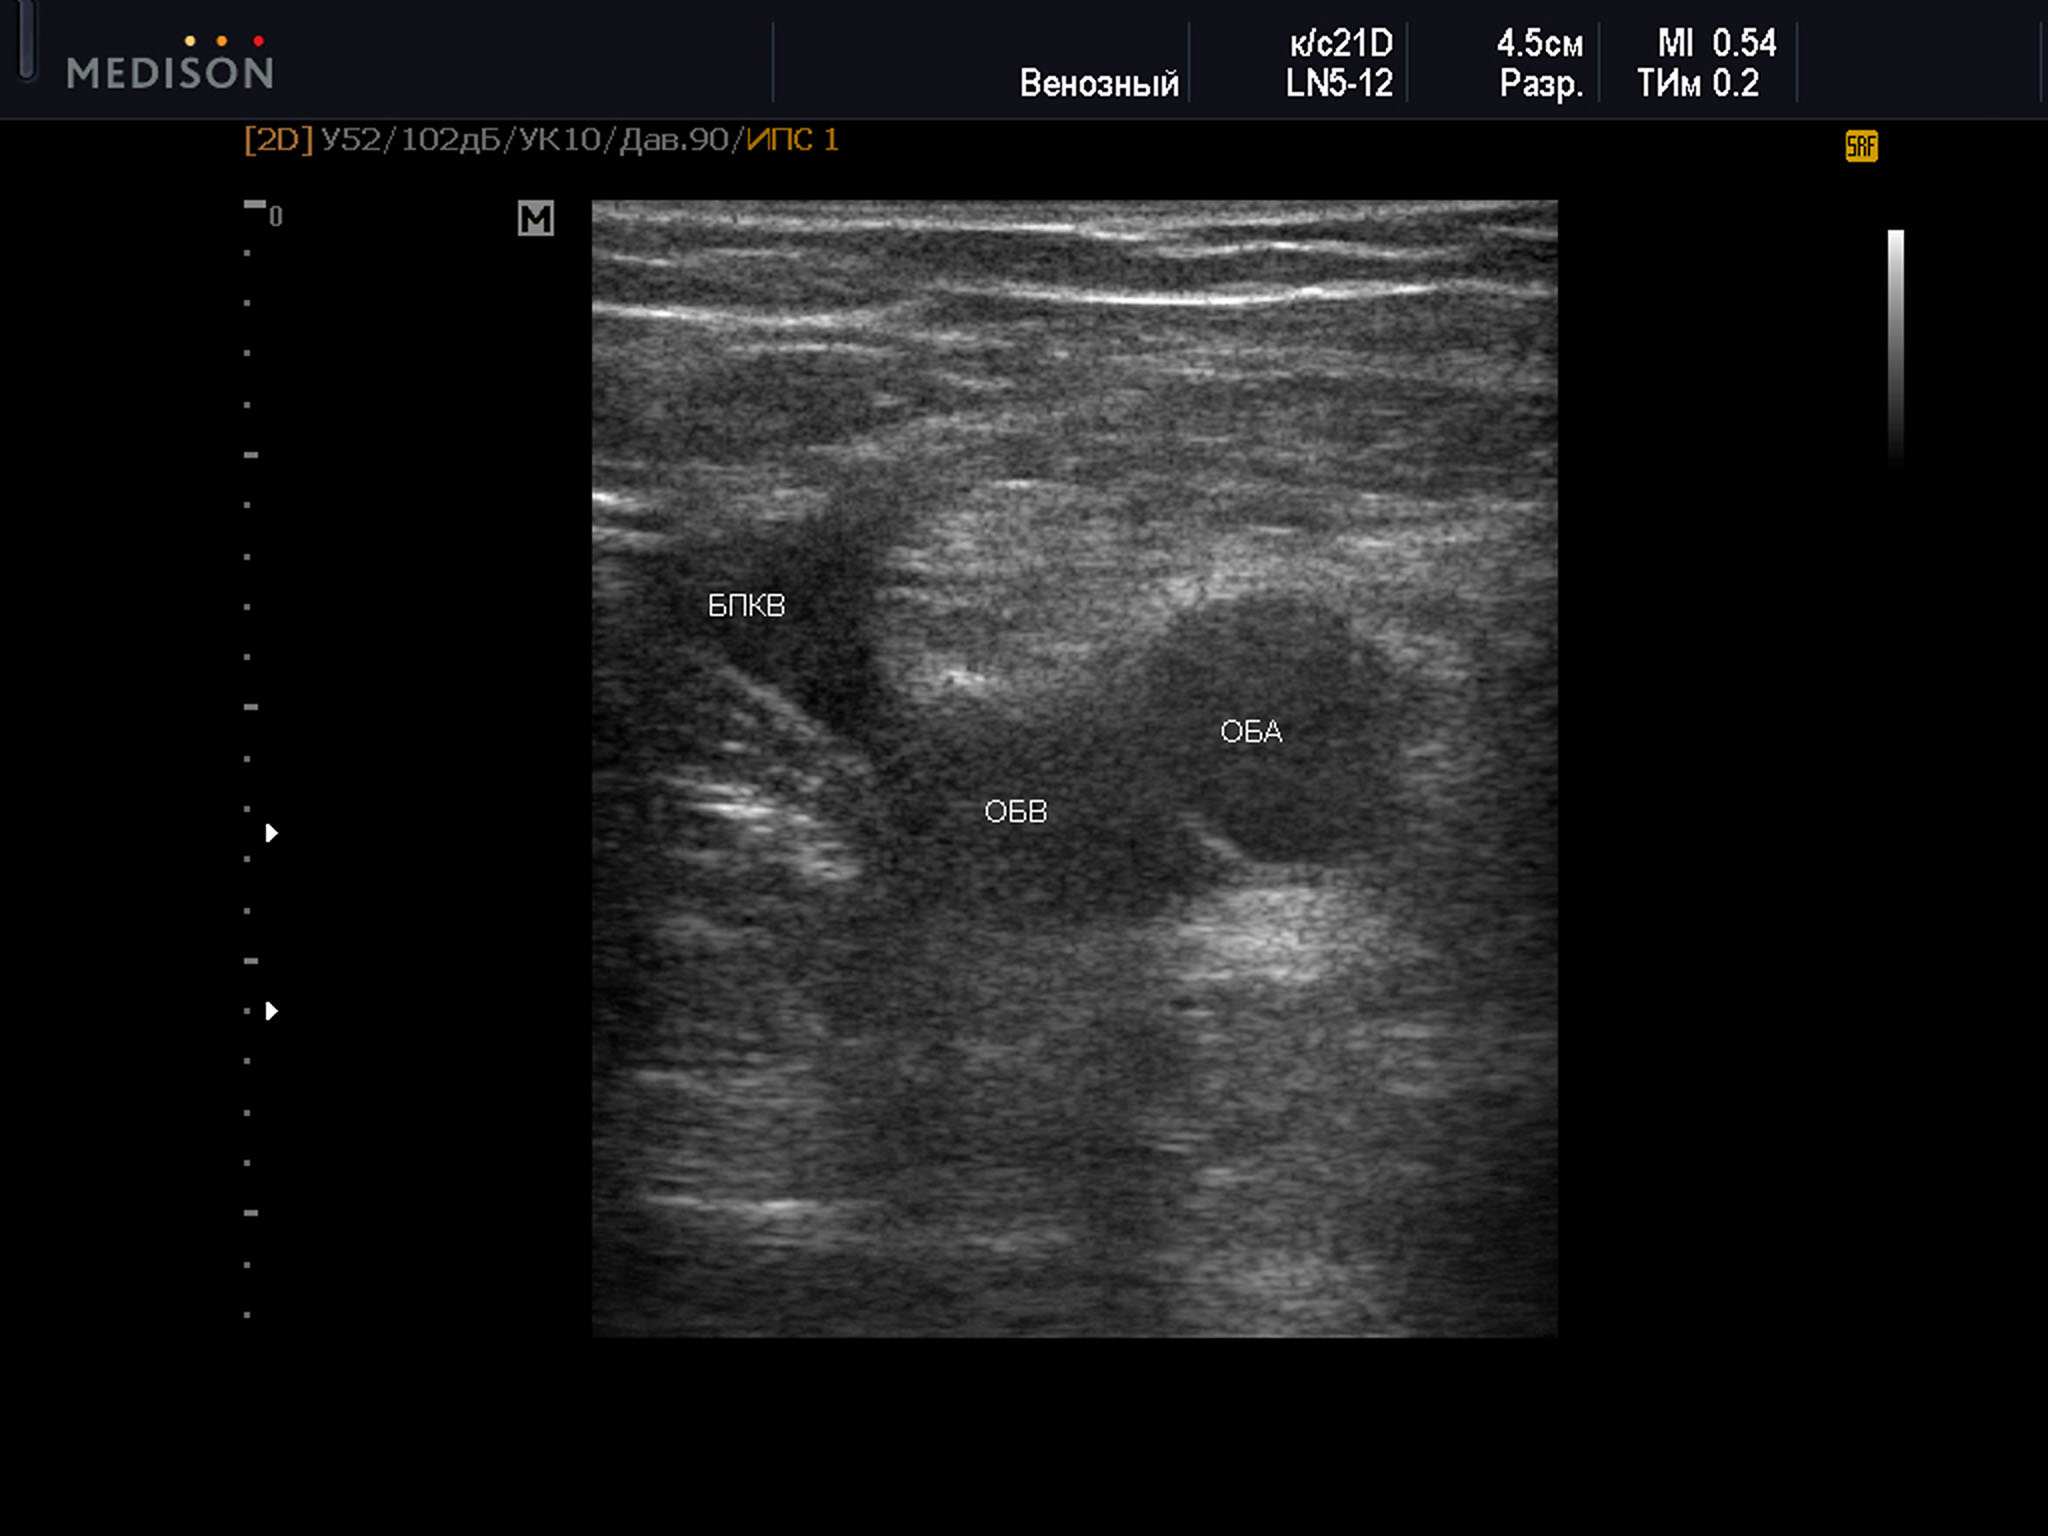

Пример диагностического ультразвукового изображения на уровне верхней трети бедра, поперечное сечение общей бедренной вены и общей бедренной артерии, Тип 4 взаимного положения сосудов

SonoAce R7, линейный датчик, женщина, 61 год.

ОБА – общая бедренная артерия; ОБВ – общая бедренная вена; БПКВ – большая подкожная вена бедра

4 тип оказался самым редким — всего 7,8% от общего числа наблюдений. Из них 6,1% были выявлены справа, а 9,6% — слева. У женщин данный вариант положения сосудов выявлен в 9,2% всех наблюдений. Справа он выявлен в 7,5%, а слева в 11,1% случаев. В группе мужчин такой тип взаимного положения сосудов выявлен в 5,7% всех наблюдений. Справа в 4,3% наблюдений, а слева в 7,3% среди мужчин. Возраст всех участников был с данным типом положения сосудов от 28 до 77 лет — 53,3±12,9 лет, среди женщин возраст был от 38 до 77 лет — 58,3 ± 12,0 лет, возраст мужчин был от 28 до 57 лет — 41,2 ± 9,4 года.